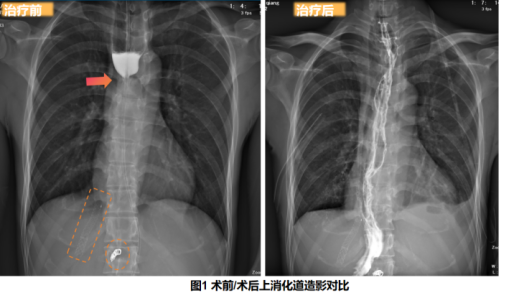

手术采用“食管旷置术+胃代食管旁路重建+颈部食管-胃吻合术”,将管状胃经胸骨后通道上提至颈部与颈段食管完成吻合,从根本上绕开狭窄段建立新的通路。术中可见门脉高压相关改变明显,血管迂曲扩张、侧支循环丰富,脾脏显著肿大,解剖层次受影响,术野暴露困难、操作空间受限,出血风险及止血难度显著增加。此外,为提高旁路通道建立的安全性与可视化程度,袁勇教授团队在建立胸骨后通道过程中采用腔镜辅助,强化对通道层次及周围重要结构的辨识与保护,降低盲性分离带来的潜在风险。在精细化操作与周密止血策略、严密麻醉管理保障下,手术顺利完成。

赵先生术后恢复平稳,即将开始逐步过渡至经口进食。该手术的成功,为内镜治疗失败、合并肝硬化门脉高压及食管气管瘘等高风险人群的顽固性食管狭窄提供了可借鉴的外科重建路径。